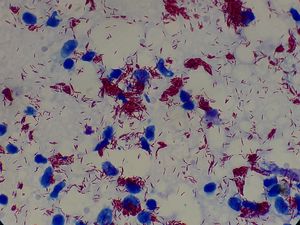

:피부를 수직으로 절개하여 조직 도말을 슬라이드 글라스에 놓고 칠-닐슨 염색(Ziehl-Neelsen stain)으로 균수를 검사하는 것이다. 칠-닐슨 염색은 항산성 염색의 한 방법으로 나균을 붉게 염색한다. 피부를 절개하므로, 통각이 정상적인 부위에서는 통증을 동반하기 때문에, 국소 마취를 한 후 검사를 실시한다. 균수 표기에는 '''세균 지수(BI: bacterial index)'''가 사용된다. BI는 MB형·PB형 분류 및 치료 방침에서 중요하다. 또한, 이전에는 형태 지수(MI: morphological index)를 측정하여 균의 종합적인 힘을 보는 방법도 있었지만, 2011년 시점에서는 시행되지 않는다.

:피부를 수직으로 절개하여 조직 도말을 슬라이드 글라스에 놓고 항산성 염색의 한 방법인 칠-닐슨 염색(Ziehl-Neelsen stain)으로 균수를 검사한다. 이 염색법은 나균을 붉게 염색한다.[3] 피부 절개 시 통증이 있을 수 있어 국소 마취 후 검사한다. 균수 표기에는 '''세균 지수(BI: bacterial index)'''가 사용되며, 이는 MB형·PB형 분류 및 치료에 중요하다.[3]